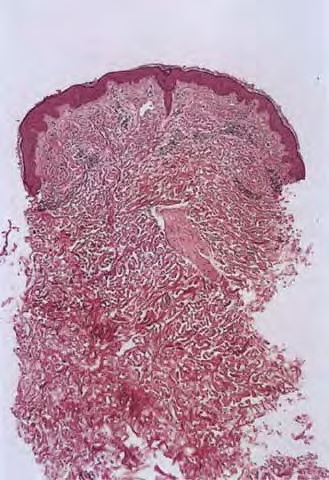

morbilliform-viral-exanthem